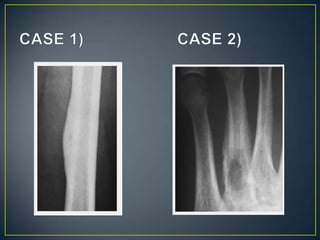

• The type of bone destruction caused by a tumor is

primarily related to the tumor growth rate.

• Not pathognomonic for any specific neoplasm.

• Geographic.

• Moth Eaten.

• Permeative.